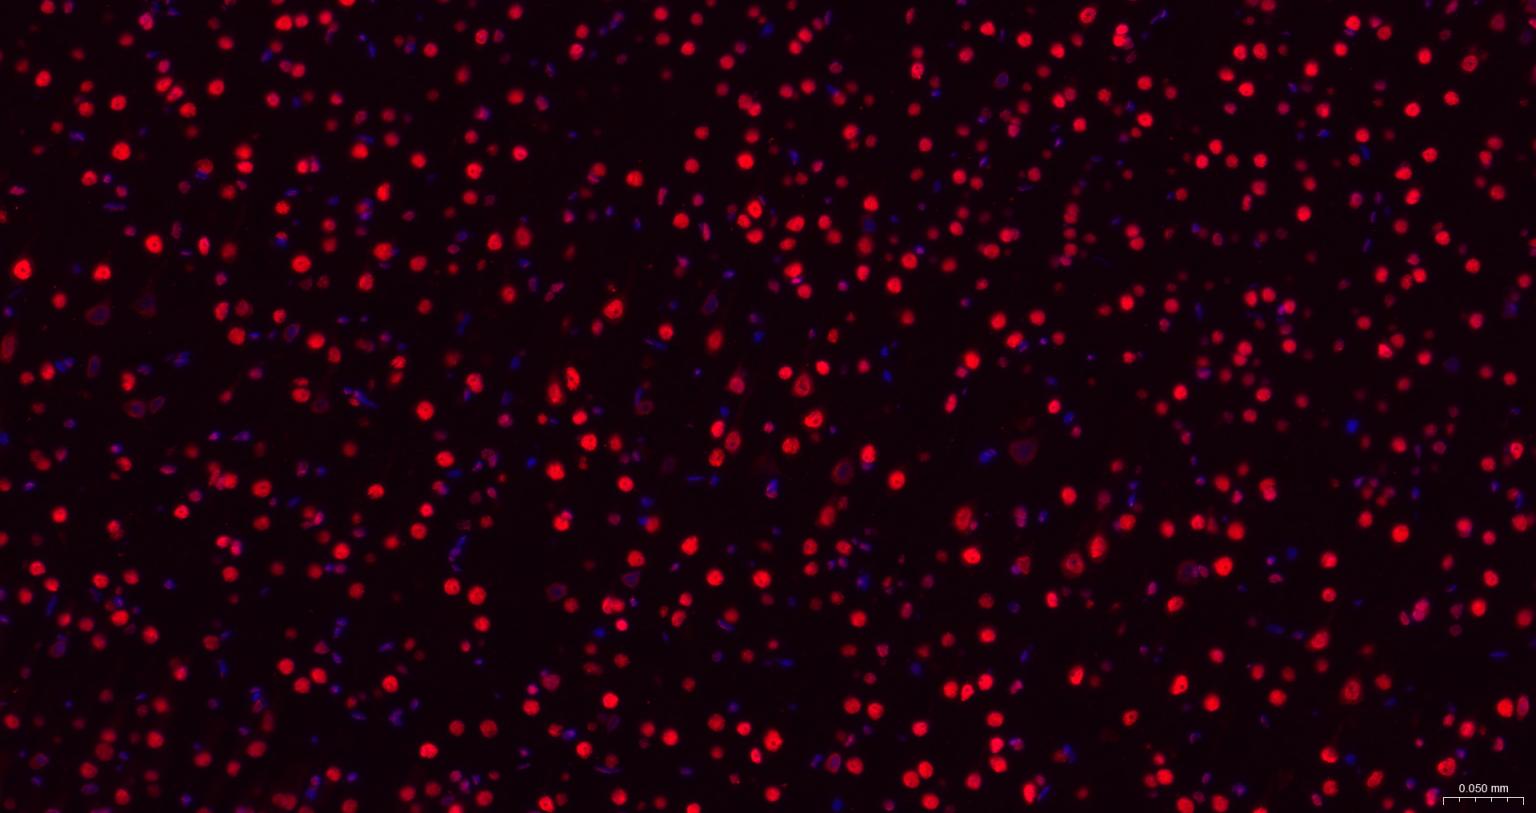

Paraformaldehyde-fixed, paraffin embedded Mouse Cerebrum; Antigen retrieval by boiling in sodium citrate buffer (pH6.0) for 15 min; The section was incubated with TARDBP Monoclonal Antibody, Unconjugated (bsm-60837R) at 1:200 overnight at 4°C. Followed by conjugated Goat Anti-Rabbit IgG antibody (Red, bs-0295G-BF594), DAPI (blue, C02-04002) was used to stain the cell nuclei.